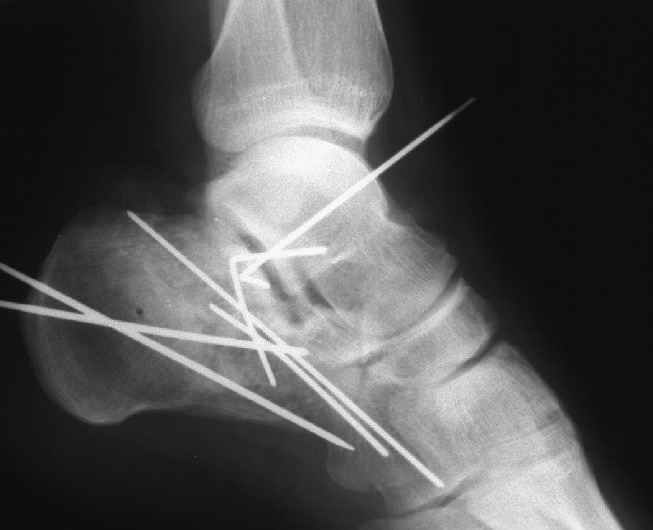

представляю снимки пациента с переломом пяточной кости. послеоперационный снимок этапный - по снятии швов спицы удаляю и наладываю циркулярную гипсовую повязку. к сожалению снимки с удаленной скобой представить не могу но поверьте на слово - консолидация полная, коррекция стойкая.

при планировании операции и ее исполнении выполнена костная аутопластика трансплантатом с гребня подвздошной кости причем трансплантат брался фрезой размером несколько болишим чем образованный в результате травмы дефект. скоба в данном случае обеспечивает компрессию между отломками-трансплантатом